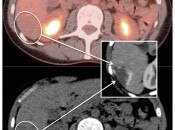

The normal liver demonstrates diffuse FDG uptake (typically greater than or equal to the spleen).

Many readers consider the uptake in the liver to represent the “background metabolic activity” for an exam.

For assessment of many lesions found in the body, the metabolic activity of the liver serves as the reference threshold by which to decide what is benign (uptake < liver) and what is malignant (uptake > liver).

Focal increased FDG uptake in the liver is always highly suspicious for malignancy. Very commonly, these malignant lesions may be poorly delineated on the co-registered CT images due to the lack of intravenous contrast administration.

Non-avid, low attenuation liver lesions are almost always benign (usually representing cysts, hemangiomas or fully treated malignant lesions), although some hepatocellular carcinomas can demonstrate only very mild metabolic activity.